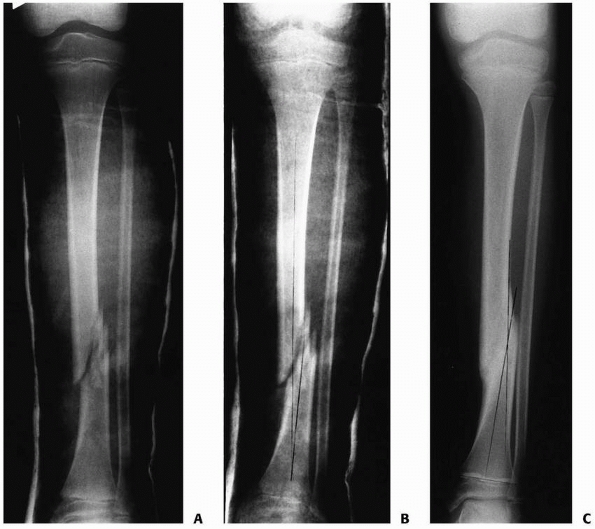

isolated tibial fractures within the first 2 weeks after injury (Fig. 25-10).153

In these cases, the forces of contraction of the long flexor muscles of

the lower leg are converted into an angular moment by the intact fibula

producing varus malalignment (Fig. 25-11A).

![]() |

|

FIGURE 25-10 Anteroposterior radiograph of a distal one third tibial fracture without concomitant fibular fracture in a 10-year-old child. A. The alignment in the coronal plane is acceptable (note that the proximal and distal tibial growth physes are parallel). B. A varus angulation developed within the first 2 weeks after injury. C. A 10-degree varus angulation was present after union.